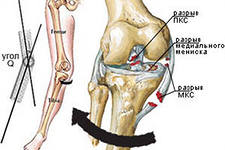

разрыв сухожилий или связок колена (боковых, крестообразных) либо надколенника (рис 3);

Рис. 3 Разрыв передней крестообразной,

внутренней боковой связок,

внутреннего мениска -